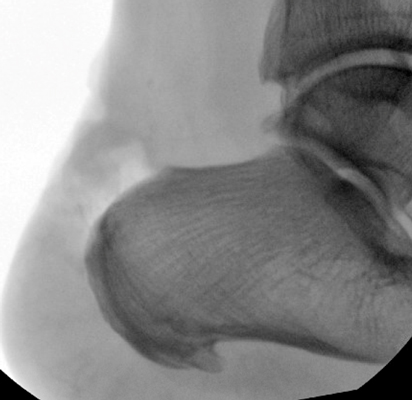

TOTAL ANKLE REPLACEMENT :: ORIF CALCANEUS :: ORIF ANKLE FRACTURE DISLOCATION :: COMPLEX BUNION AND LESSER TOE CORRECTION :: TALUS FRACTURE -1 :: TALUS FRACTURE -2 :: LISFRANC REPAIR :: COMPLEX TRIPLE ARTHRODESIS 1 :: COMPLEX TRIPLE ARTHRODESIS 2 :: MINIMALLY INVASIVE BUNION REPAIR 1 :: MINIMALLY INVASIVE BUNION REPAIR 2 :: ARTHROSCOPIC CARTILAGE REPAIR :: TENEX SPUR DEBRIDEMENT :: Haglunds Debridement and Achilles Repair